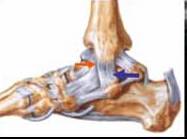

LIGAMENT FIBULOCALCANEAN

Este fascicolul mijlociu al ligamentului

lateral al gleznei. Este o structura

hiperecogena liniara → bine delimitata

care se plaseaza intre fibula si calcaneu

Serveste de hamac pentru tendonul

Fibular scurt si lung →

De notat un mic epansament subtalian